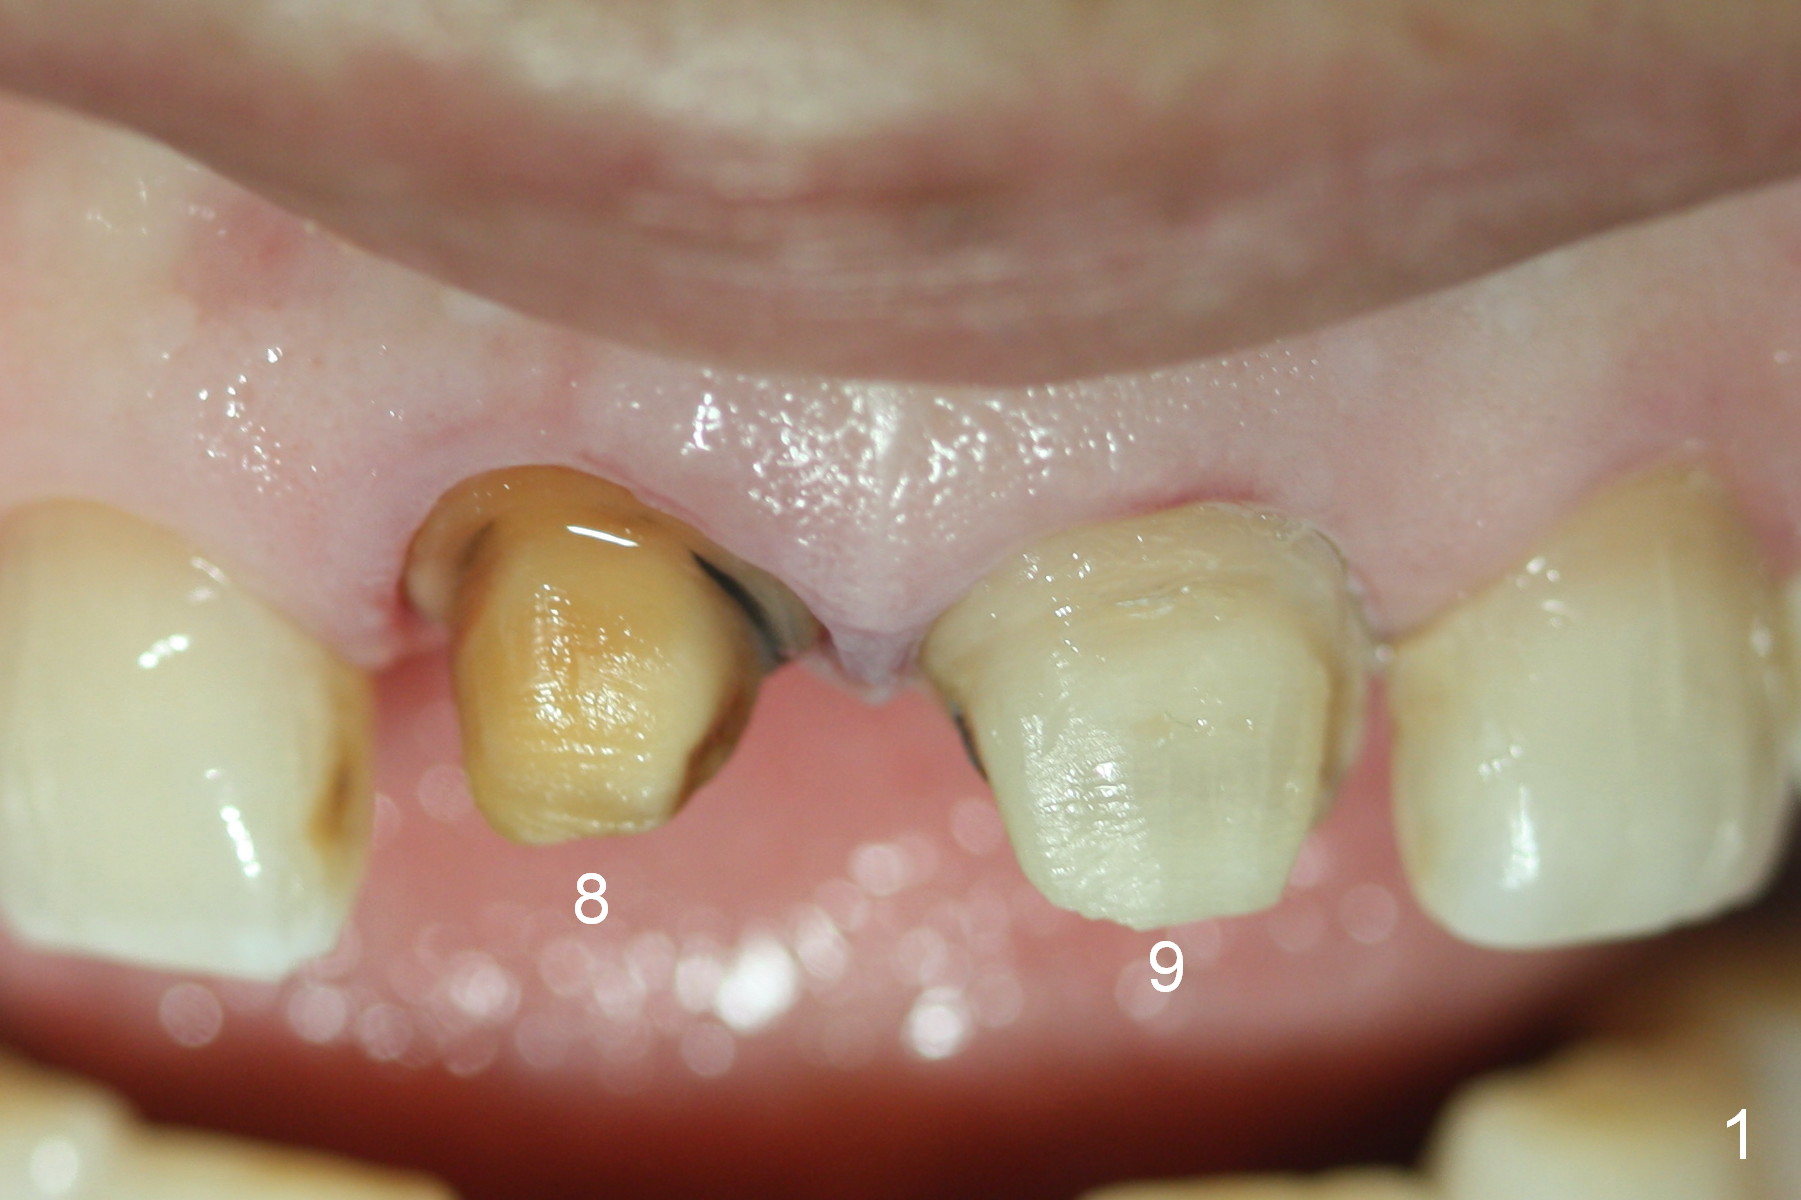

A 54-year-old lady (CL) has a discolored central incisor (#8, Fig.1). Stump shade is shown in Fig.2. Other reference shades are shown in Fig.3-5.